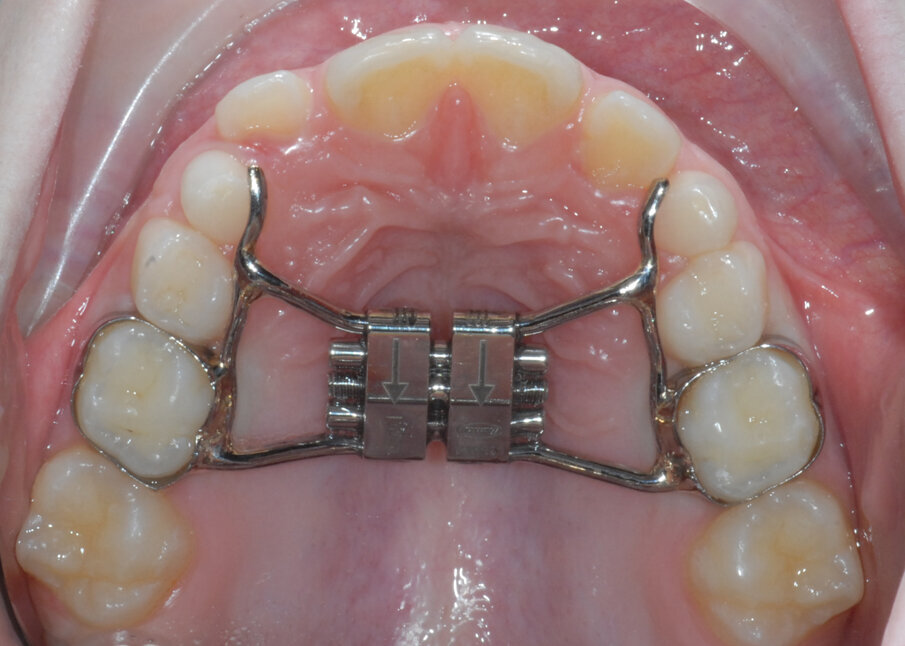

Riccardo, 6 anni

Riccardo 6 anni, viene sottoposto in prima visita ad ortopantomografia (Figg. 12, 13) delle arcate dentarie che evidenzia un deficit di spazio per l’eruzione dei canini permanenti. Si acquisiscono i modelli virtuali tramite scanner intraorale, viene fatta la prova bande e viene realizzato un espansore del palato modello Leaf expander® (Leone, Sesto Fiorentino (FI), Italia). L’espansore viene cementato su “E” (Fig. 14).

Al termine dell’espansione calibrata del mascellare superiore (Fig. 15), vengono presi dei nuovi modelli virtuali con i quali si realizza una barra di Nance (Figg. 16, 17) customizzata in Trilor® (Bioloren, Seregno, Italia). Il Trilor è una resina rinforzata con fibre, ha la caratteristica di essere molto leggera ed ha una rigidità ottimale; ciò consente il suo impiego in sostituzione del metallo per la fabbricazione di diversi device ortodontici.

Fig. 14_Leaf expander cementato.

Fig. 15_Leaf expander al termine dell’espansione.

Fig. 16_Progetto CAD della barra di Nance customizzata.

Fig. 17_Nance realizzata in Trilor.